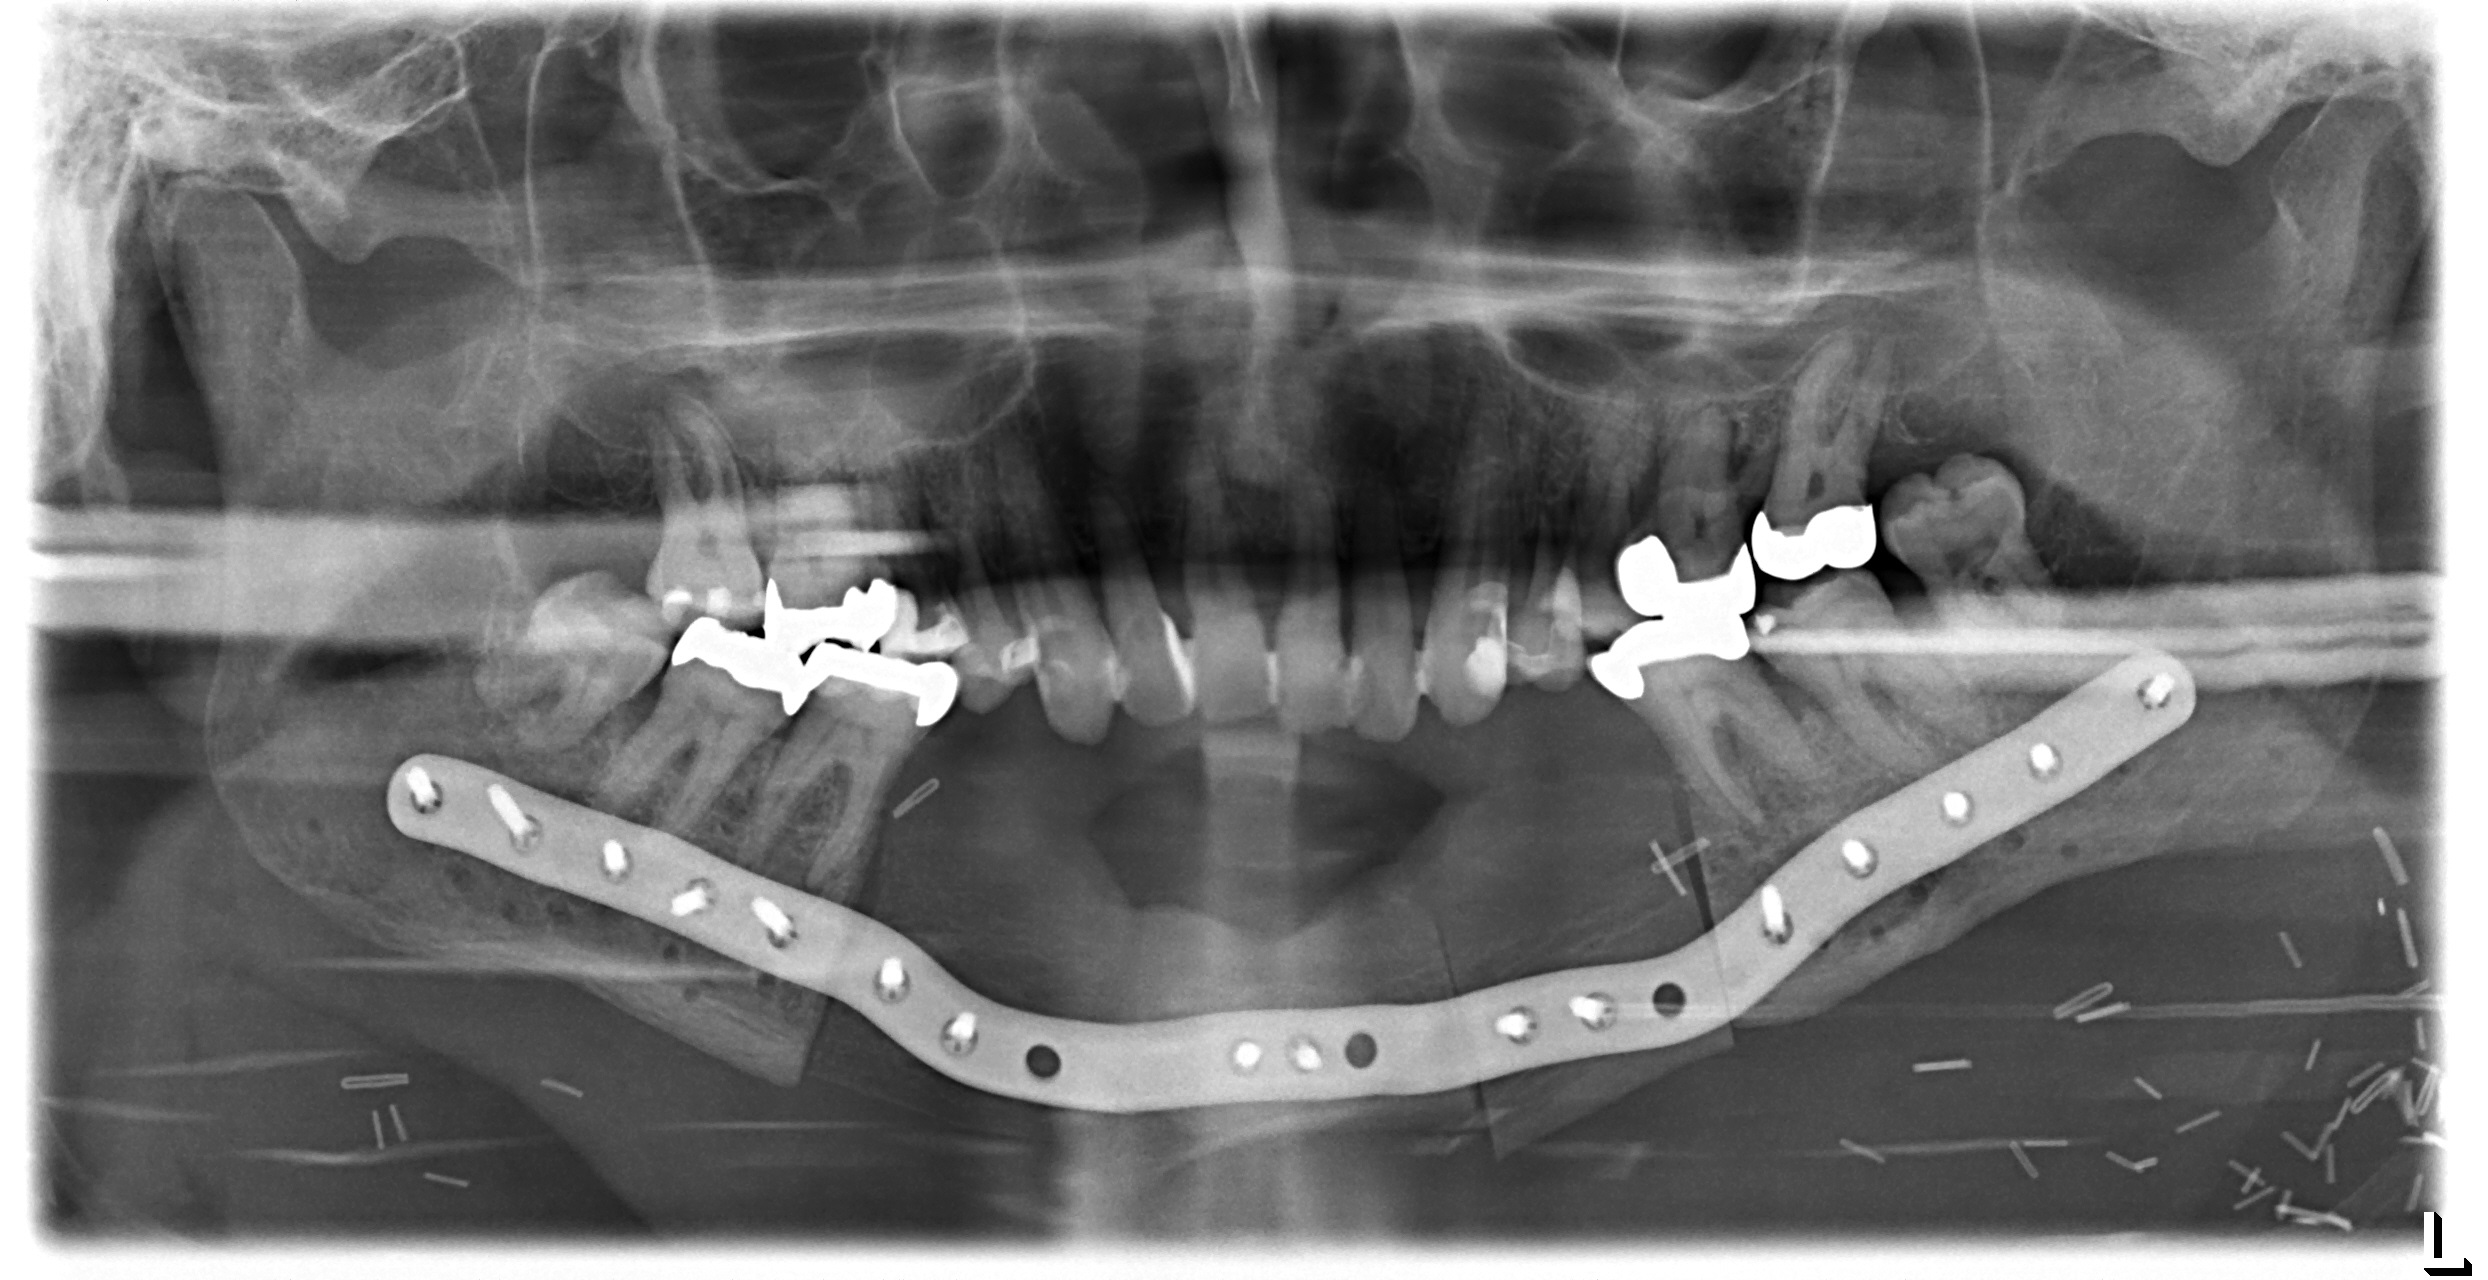

Scapular SLS templates or cutting guides were manufactured for secondary resection of the mandibular bone stumps, along with a set of STL models and a patient specific mandibular reconstruction plate (PSMP) (Fig. 5).

Postoperative imaging confirmed minimal intersegmental gaps to the mandibular remnants with undisturbed healing but limited overall bone volume (Fig. 7a-c). Therefore removal of the PSPMP and a preimplantological augmentation with corticocancellous iliac bone grafts followed 16 months later.

Finally, dental implants were inserted (Fig. 8).